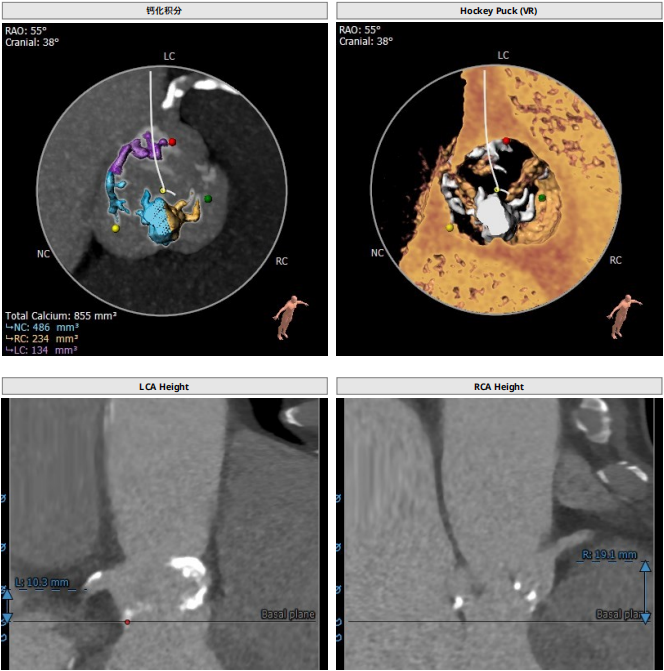

由于患者主动脉瓣根部结构钙化严重,右无冠窦瓣叶钙化融合且融合位置高及窦管交界,冠脉风险高介入手术难度很大,入路上陈旧性夹层是生命通路上的又一道关卡。TAVR手术极大的考验术者及团队的综合能力,团队术前制定详细的手术方案及应急预案确保手术顺利进行,为患者带来新生的机会。

12月31日首都医科大学附属北京同仁医院心血管中心郭彩霞教授团队顺利完成首例TAVR手术。术中22mm球囊预扩冠脉不显影随即进行左冠冠脉烟囱支架保护,植入VenusA Plus可回收L26瓣膜,植入后位置良好,跨瓣压差近乎为零,整个手术一气呵成,手术取得圆满成功,手术后患者状态良好,成功救治82岁高龄患者。体现了心血管中心团队的综合救治能力,标志着在结构性心脏病的微创治疗方面达到国内先进水平。